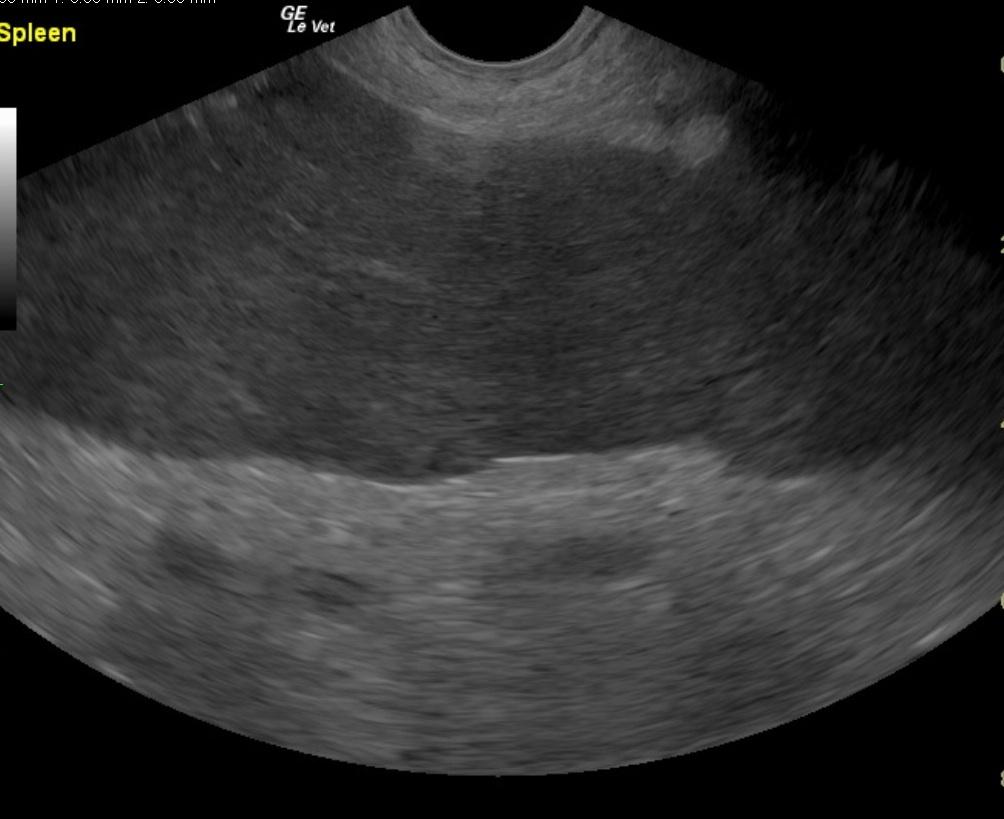

A 6-year-old intact male English Bulldog was presented for 2-3 days of intermittent vomiting and lethargy. Physical exam found the patient to be tachycardic with pale mucous membranes and a palpable mass in the abdomen. Serum biochemistry revealed elevated alkaline phosphatase, hypernatremia, and mild hypochloremia. On CBC, a decreased HCT in conjunction with a high MCV was noted, in addition to a neutrophilia, monocytosis and thrombocytopenia. No abnormalities were noted on thoracic radiographs. Abdominal radiographic findings revealed a loss of contrast in the cranial abdomen, with the possibility of a splenic mass. Radiographic Interpretation showed marked splenomegaly strongly suspected to be secondary to torsion, although accompanying infiltrative or neoplastic pathology could not be ruled out. The small volume of peritoneal effusion and inflammation was likely secondary to the splenic pathology. Thoracic radiographs showed mild microcardia and under perfused pulmonary vasculature in support of hypovolemia. Atypical intrathoracic fat distribution was considered to be incidental in this dog. This dog had multiple hemivertebrae.